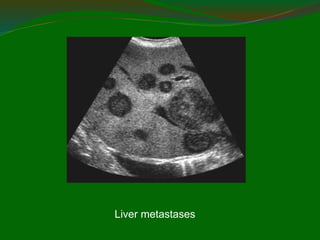

Liver metastases

www.upei.ca/~vetrad